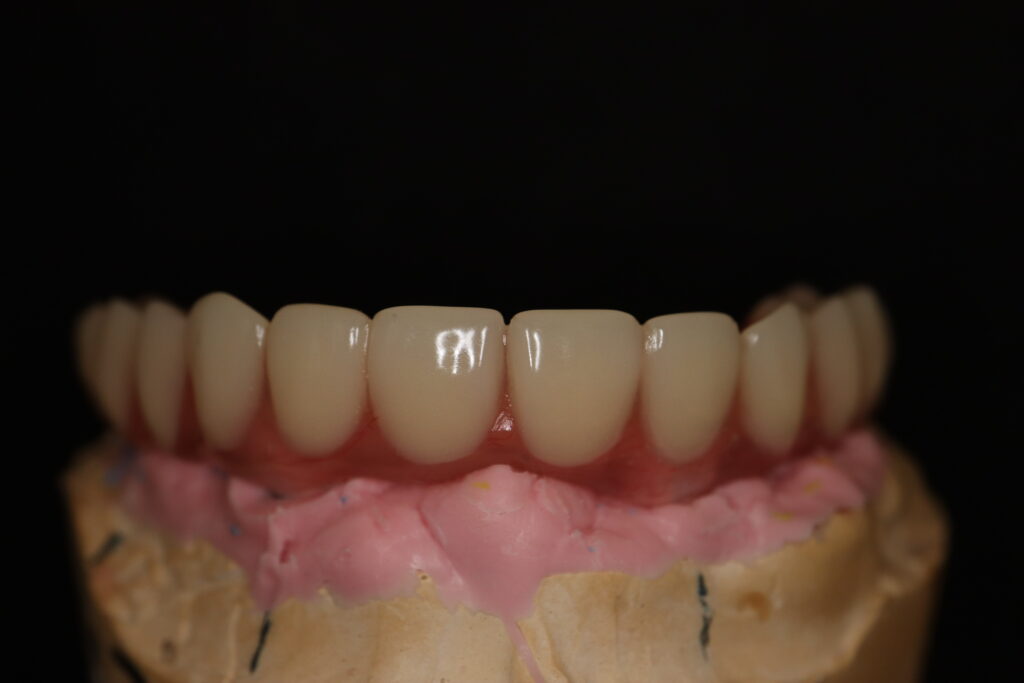

Спустя 7 дней на верхней челюсти зафиксирован металлоакриловый протез из 12 зубов с опорой на 4 дентальные имплантата.

протез